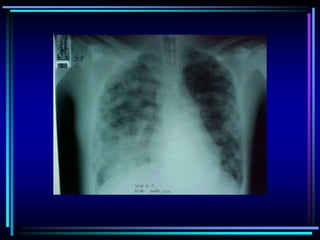

FALLA RESPIRATORIA HIPERCAPNICA

FALLA RESPIRATORIA HIPOXEMICA